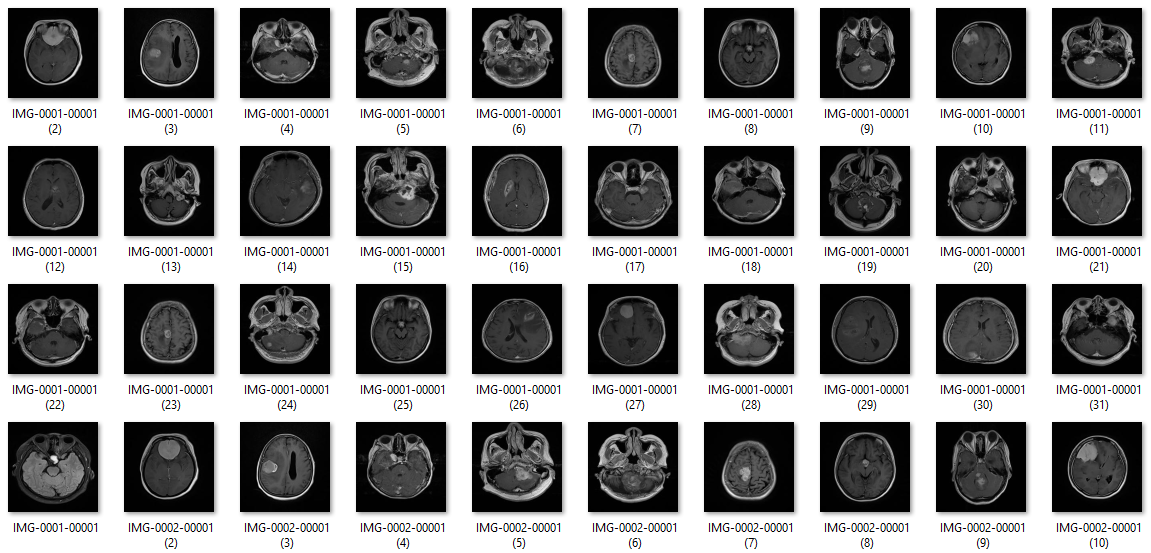

Penelitian ini mengimplementasikan metode semantic segmentation berbasis Convolutional Neural Network (CNN) arsitektur ResNet-18 pada citra MRI otak. Sebanyak 171 data citra DICOM beserta ground truth digunakan sebagai data latih untuk melatih model segmentasi. Sistem dilengkapi dengan antarmuka grafis (GUI) berbasis MATLAB yang mampu melakukan segmentasi otomatis, menghitung volume tumor, serta menampilkan visualisasi hasil dalam bentuk 2D maupun 3D.

Dataset terdiri dari 171 citra MRI otak dalam format DICOM beserta ground truth berupa mask biner tumor. Ground truth diperoleh melalui proses ROI manual menggunakan teknik freehand contouring, sehingga area tumor terdefinisi dengan baik.